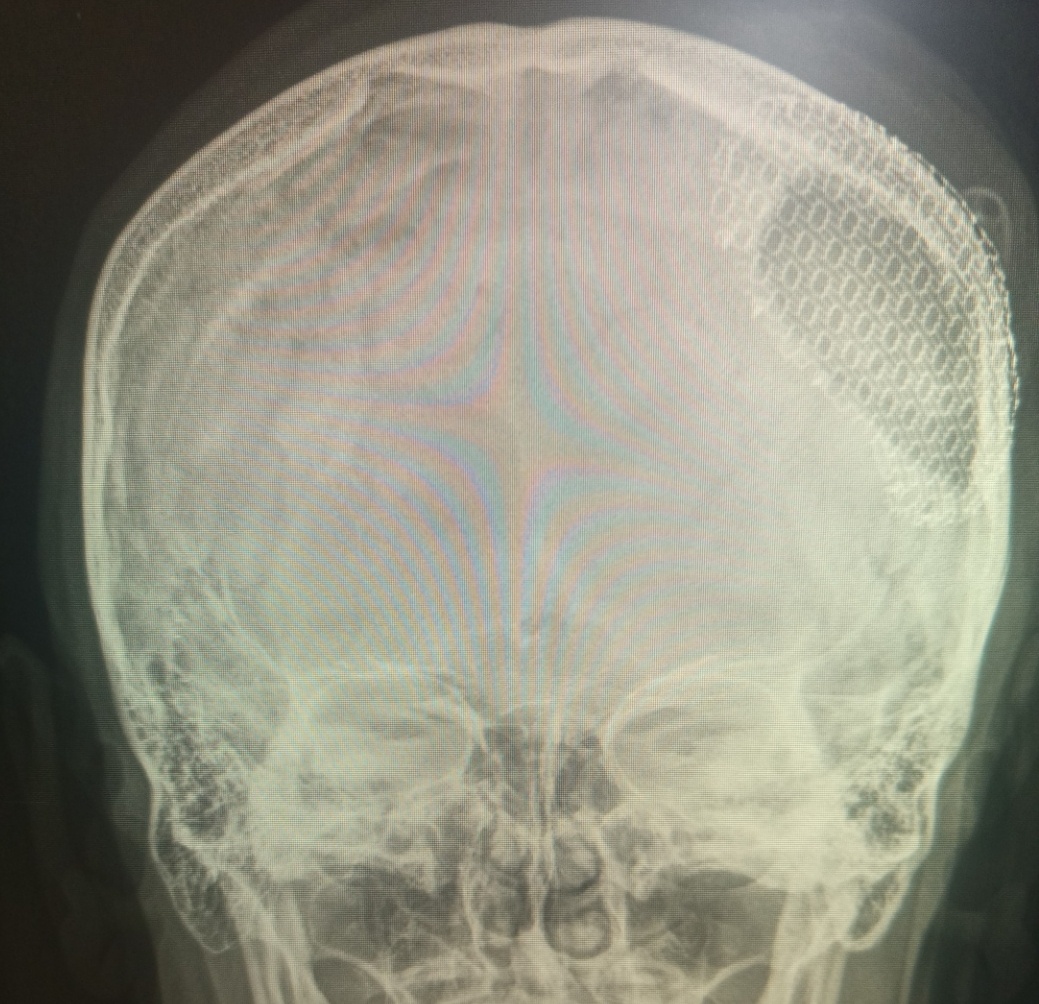

С восьми до девяти утра забрел только один нетрезвый мужчина, сказал, что голова у него болит, показал рукой на левую часть головы.

–Ну , проходите, –вздохнула я. –А травма была?

–Да давно была, теперь вот иногда болит, как выпью.

Гениально!

Сделала снимок–наш пациент, с трепанацией в прошлом и с пластиной в настоящем.

–Так у вас имплант стоит же, вы забыли что ли? –напомнила я. Волосы у него довольно густые, и сразу я не заметила дефект.

–Да помню я, это еще с 2013 года.

–А почему поставили?

–Избили меня сильно, пришлось ставить.

–Так вроде употреблять нельзя при таком заболевании?

–А какая в жизни радость еще? Ответь мне, сестренка.

Я решила не ввязываться в ненужный разговор.

–Идите обратно, снимки у врача.